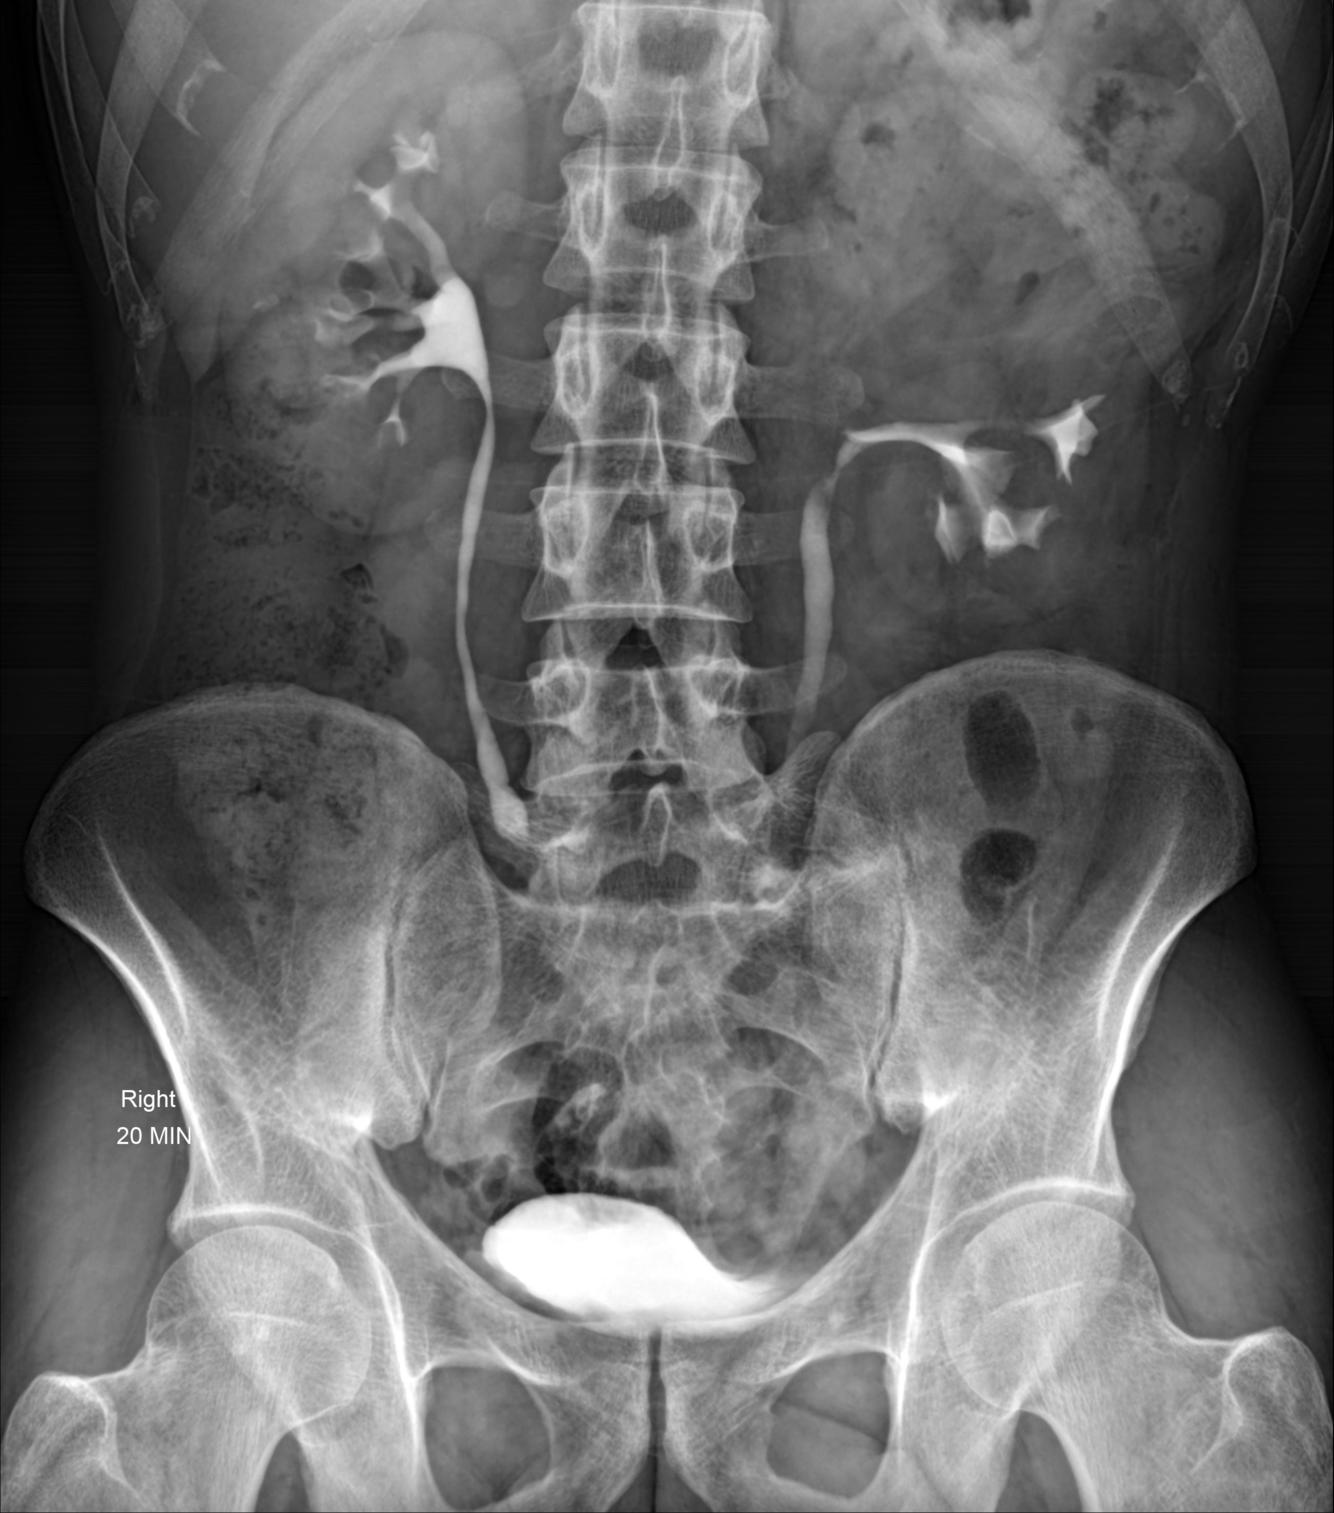

Case Discussion

Left sided duplicated collecting system with the upper moiety obstruction, and non-functioning. It displaces the lower pole moiety inferiorly, mimicking the appearance of a drooping lily.

The drooping lily sign refers to the inferolateral displacement of the opacified lower pole moiety due to an obstructed (and unopacified) upper pole moiety in duplicated collecting system.

Case courtesy of Dr Mohammad Taghi Niknejad, Radiopaedia.org, rID: 54354